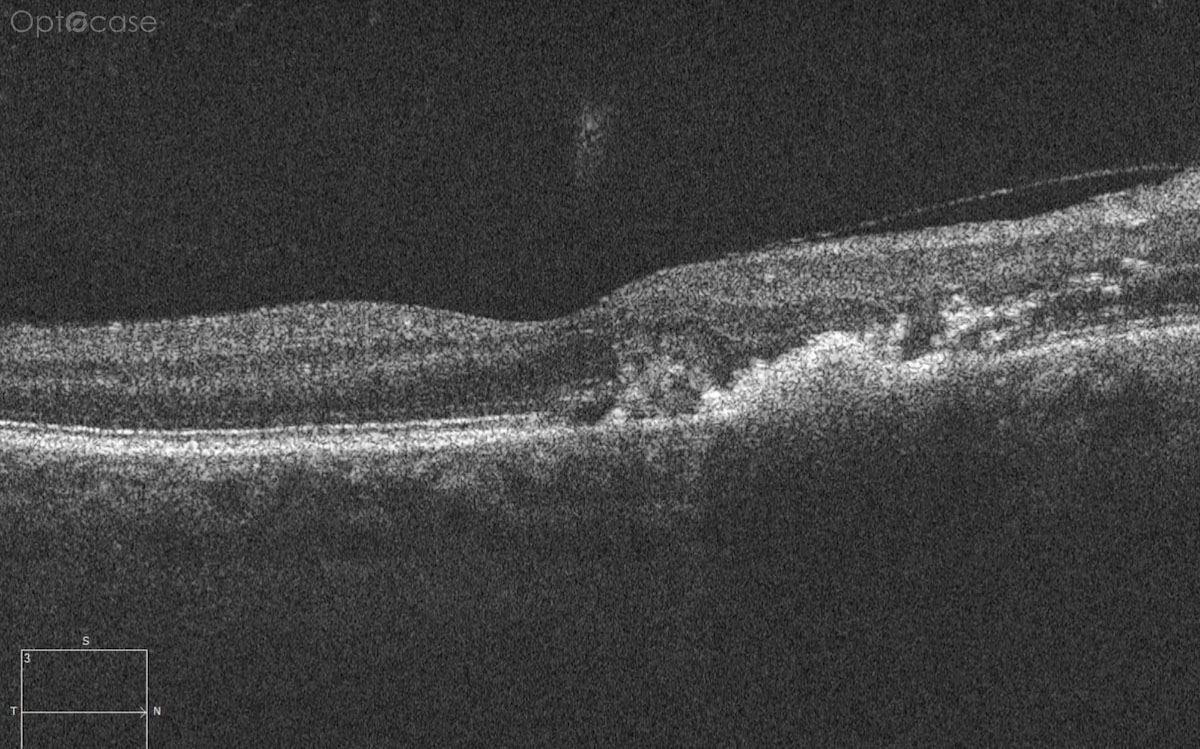

Here there is loss of the regular macular depression. There is a bright line present on the surface of the retina. In addition, there is separation of the retinal layers in the inner retina.

The patient was diagnosed with a schisis secondary to an epiretinal membrane. This complication is seen in over 50% of ERMs (video).

In any patient with intraretinal fluid consider the possibility of an epiretinal membrane causing a schisis.